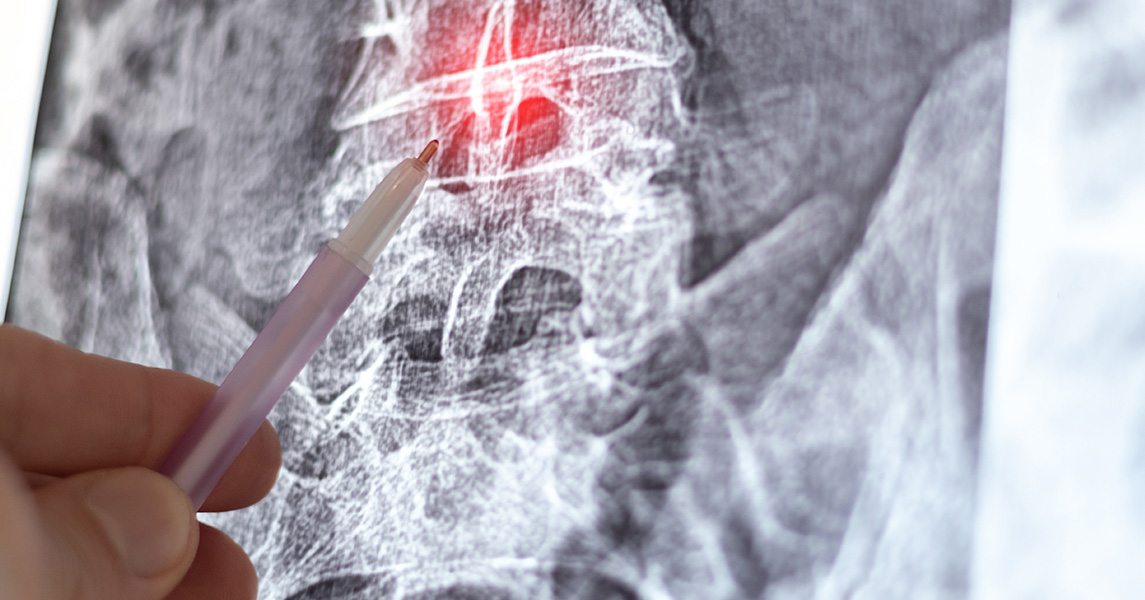

La diagnosi di spondiloartrosi richiede esami sia fisici sia strumentali. Il/la medico/a raccoglie i sintomi riferiti dal paziente ed esamina la schiena per valutare la presenza di dolore e gonfiore; successivamente, esami di imaging permettono di ottenere immagini delle condizioni interne dell’organismo, definire meglio il quadro di spondiloartrosi ed escludere eventuali altre cause dei disturbi. In particolare, l’esame di riferimento per la diagnosi di spondiloartrosi è la radiografia. Possono eventualmente essere raccomandati anche altri esami, come risonanza magnetica ed esami del sangue, sempre nell’ottica di escludere altri disturbi.